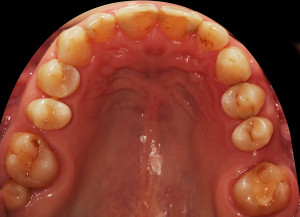

Do kliniki Stomatologia Bez Bólu zgłosiła się pacjentka, lat 61 z problemem nadwrażliwości zębów. Po przeprowadzonym wywiadzie stwierdzono spożywanie sporej ilości sezonowych owoców (truskawki, wiśnie, czereśnie, czarna porzeczka), nawet 3 razy dziennie. Następnie wykonano badanie wewnątrzustne. Stwierdzono obecność płytki nazębnej, ciemnego osadu oraz kamienia nazębnego na części trzonowców:

Wykonano higienizację jamy ustnej poprzez usunięcie kamienia nazębnego skalerem ultradżwiękowym, zdjęciem osadu i płytki nazębnej poprzez piaskowanie air flow plus oraz classic, a następnie wypolerowaniu gumką ze specjalistyczną pastą polerską:

Po wypłukaniu jamy ustnej przez pacjentkę rozcieńczonym eludril classic przystąpiono do fluoryzacji preparatem clinpro varnish. Odizolowano wałeczkami ligniny zęby od śliny aby zapewnić ich suchość, a następnie pędzelkiem nałożono preparat na wszystkie zęby:

Celem fluoryzacji jest zmniejszenie nadwrażliwości zębów oraz wzmocnienie ich przez odbudowę mikroubytków szkliwa.